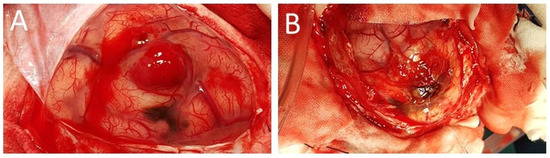

2. Case Presentation